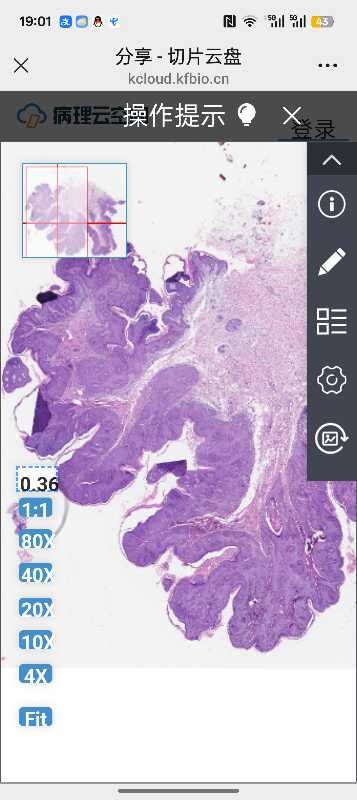

皮肤肿物

性别

男

年龄

34

临床诊断

肿物

一般病史

肿物3年

标本名称

腹股沟肿物

大体所见

乳头状肿物2枚

请老师们帮忙看看考虑尖锐湿疣吗?

湿疣